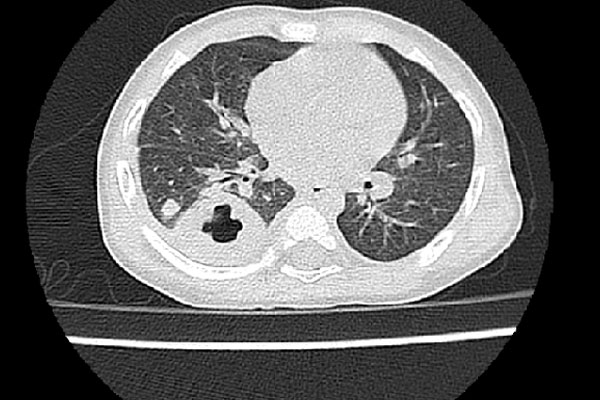

Thông tin từ khoa Nhi - Bệnh viện đa khoa Hùng Vương tiếp nhận trường hợp trẻ nhi 11 tháng vào viện vì sốt ngày thứ 7, đã điều trị tại bệnh viện huyện 5 ngày nhưng trẻ vẫn còn sốt cao từng cơn 40 độ C, trong cơn sốt trẻ rét run, ho đờm nhiều, khò khè. Nhận thấy đây là tình trạng nặng các bác sĩ khoa Nhi đã cho trẻ làm các xét nghiệm máu, chụp X-Quang tim phổi, cấy máu, chụp cắt lớp vi tính phổi.

Sau khi có kết quả, trẻ được chẩn đoán Nhiễm khuẩn huyết, áp xe phổi. Điều trị kháng sinh liều cao phổi rộng. Sau 3 ngày có kết quả cấy máu DƯƠNG TÍNH với Whitmore (Burkholderia pseudomallei).

Sau khi hội chẩn toàn viện và hội chẩn các bác sĩ Bệnh viện Nhi Trung Ương, ngoài vấn đề dùng kháng sinh điều trị bệnh, trẻ còn cần phải can thiệp các phẫu thuật ngoại khoa dẫn lưu mủ trong phổi nên đã thống nhất chuyển trẻ về tuyến trung ương điều trị tiếp.